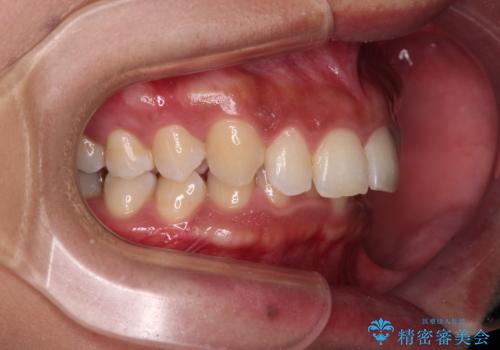

抜歯矯正で口が閉じやすく|ディープバイトと叢生を改善した症例

- 下顎前歯部には叢生が認められ、口を自然に閉じにくい状態でした。また、噛み合わせが深い「ディープバイト」の状態で、見た目だけでなく将来的な奥歯への負担も懸念されました。

口元の突出感を改善するため、上下左右の小臼歯4本を抜歯する矯正治療を計画しました。